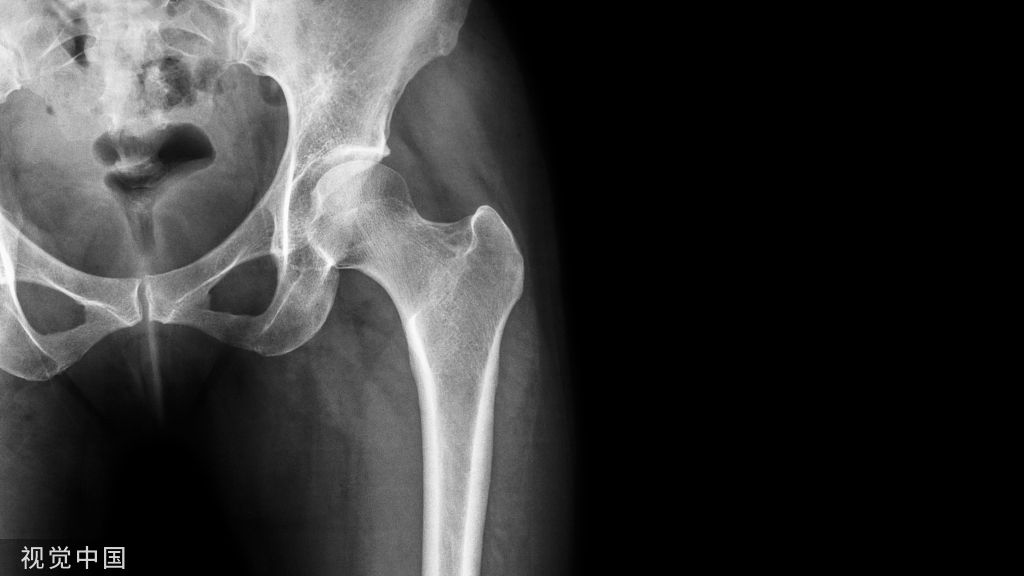

Pemberton截骨术!